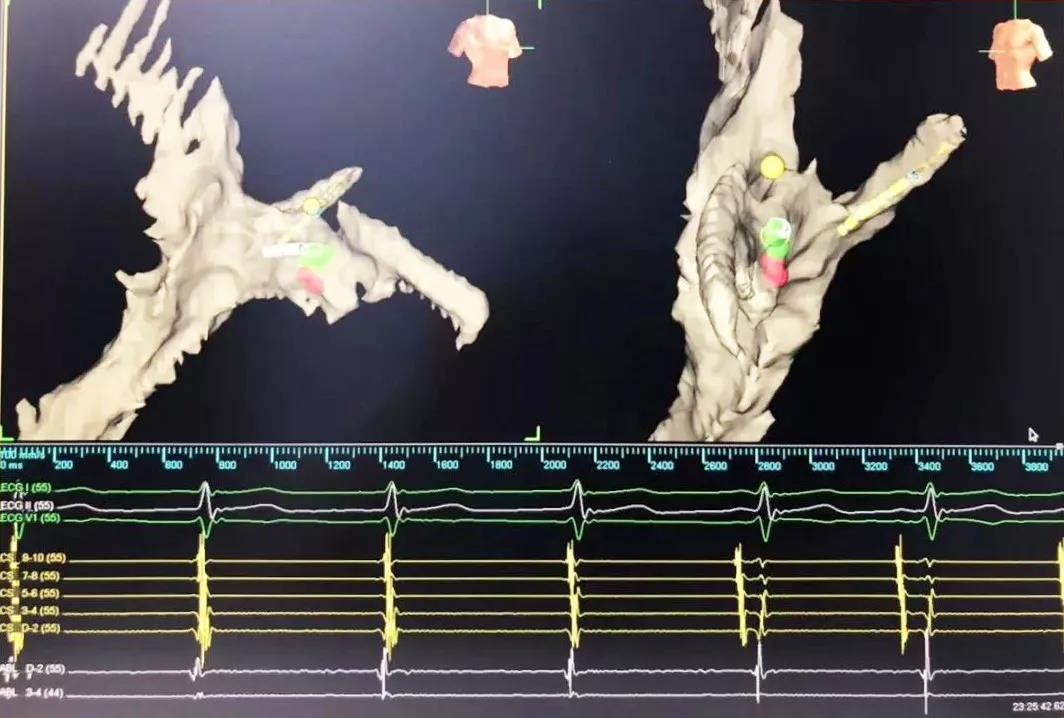

又一道難題擺在眼前,常規(guī)手術(shù)需要在X射線下進(jìn)行,X射線會(huì)導(dǎo)致胎兒發(fā)育畸形。在心臟病醫(yī)院院長(zhǎng)王海昌的帶領(lǐng)下,專家團(tuán)隊(duì)仔細(xì)研究后,決定為張女士施行三維標(biāo)測(cè)系統(tǒng)指引下零射線心臟電生理檢查及射頻消融術(shù)。

在完成常規(guī)檢查,排除新型冠狀病毒肺炎的可能后,217日,由廉誠(chéng)主刀,在三維標(biāo)測(cè)系統(tǒng)指引下行零射線心臟電生理檢查及射頻消融術(shù)。術(shù)中明確患者心動(dòng)過(guò)速為房室結(jié)折返性心動(dòng)過(guò)速,遂行房室結(jié)慢徑改良,消融完畢后反復(fù)刺激驗(yàn)證,心動(dòng)過(guò)速均不能誘發(fā),手術(shù)成功,歷時(shí)約1小時(shí),全程零射線完成。這也是西安國(guó)際醫(yī)學(xué)中心醫(yī)院心臟病醫(yī)院的首例零射線治療特殊人群心律失常病例。